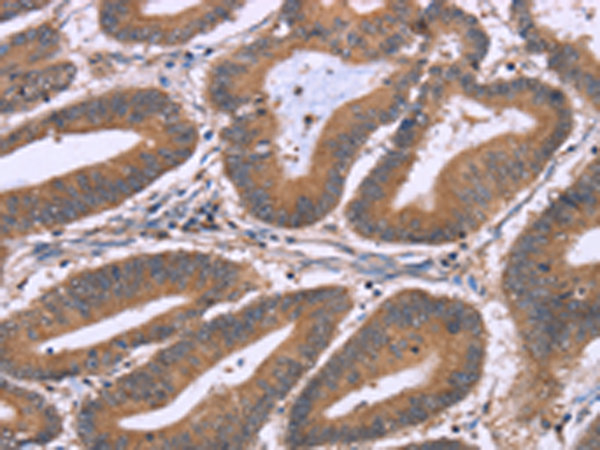

分类: 科研抗体货号: P11849别名: MDA1; NG.1; ZMDA1; IL-10C应用: WB,IHC反应种属: Human